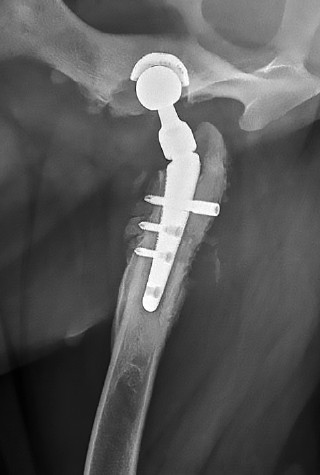

Исследования явились результатом длительного поиска надежной стабилизации импланта и поэтапной его остеоинтеграции, ведь совершенствование технологии эндопротезирования это повышение стабильности фиксации, снижение риска инфекций и улучшение биосовместимости имплантов. В этой связи, согласно клиническому опыту авторов, при соблюдении порядка введения винтов по технологии компании Kyon, частота осложнений в виде асептической нестабильности ножки эндопротеза составляет 8 % (рис. 2). К рентгенологическим признакам нестабильности относятся: перелом или миграция импланта, выраженный остеолиз вокруг ножки, а также периостальная и эндостальная костная реакция. Ранее для фиксации бедренного компонента (ножки) V@art размеров M и L применяли 5 винтов, включая один бикортикальный. Однако, на практике установка дистального винта в отверстие № 5 вызывала технические трудности. После отказа от его использования, частота асептической нестабильности не возросла. Дополнительное введение второго проксимального бикортикального винта привело к значительному снижению риска нестабильности (менее 1 %), а также улучшило равномерное прилегание ножки к медиальному кортикальному слою (рис. 1).

Рис. 1. Послеоперационная рентгенография проекция «Йога»

Источник: составлено А.М. Пантюлиным, И.Ф. Вилковыским.

Fig. 1. Postoperative radiography, “Yoga” projection

Source: compiled by A.M. Pantyulin, I.F. Vilkoviskiy.